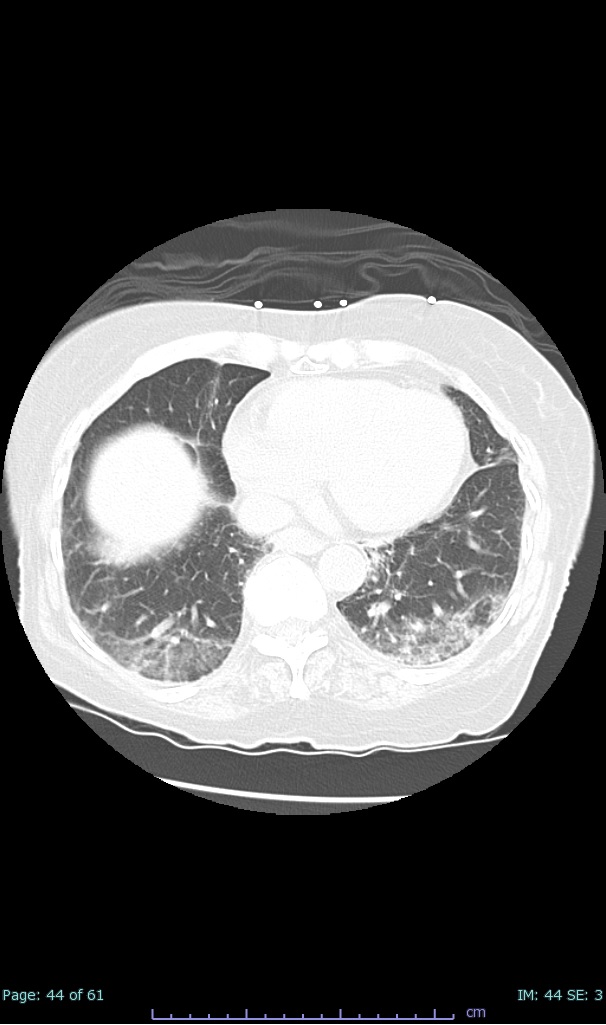

- 100% subpleural involvement, 33% + centrolobular involvement

- 40% even apical/basilar, 27% basilar dom, 5% mid dom. 1/17